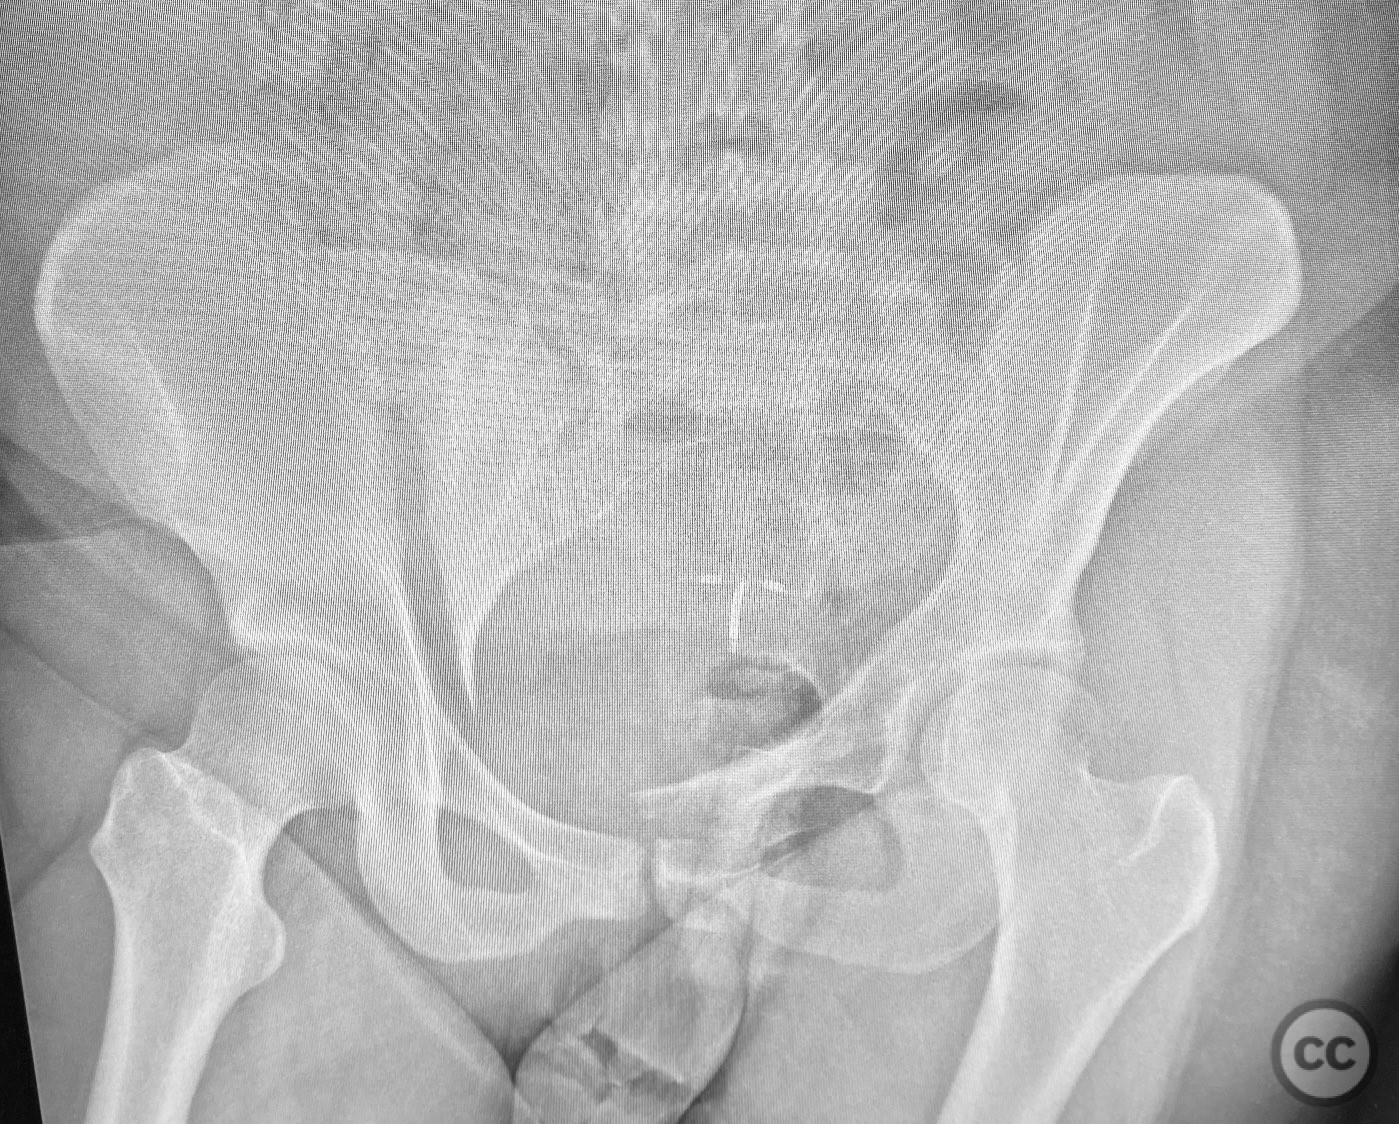

Pelvic Ring - AO/OTA 61x

Pelvis - AO/OTA 6x